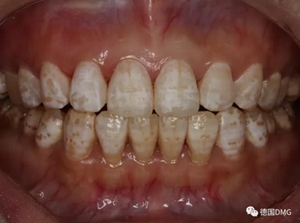

(下圖是拋光完成)

治療完成的上頜牙齒和未治療的下頜牙齒形成明顯對比。